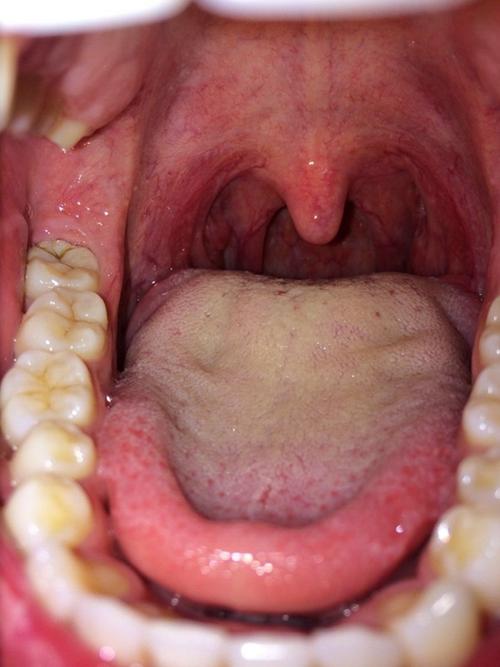

正常的扁桃体高清图片

正常的扁桃体高清图片,小孩扁桃体发炎的图片

正常人的扁桃体图片

正常人的嗓子图片

正常的扁桃体 真人

正常人的喉咙结构图

扁桃体正常和发炎对比

正常的扁桃体 儿童

正常扁桃体形状图片

扁桃体正常状态图片

成人正常的扁桃体图片

健康扁桃体高清图片

健康扁桃体图片

正常的扁桃体真人图片

正常扁桃体图片 真实